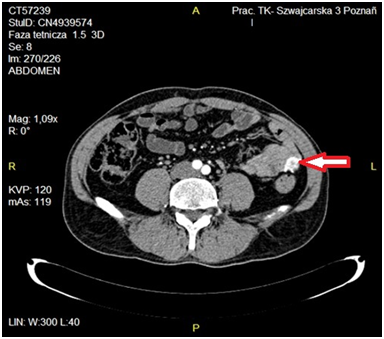

A 54-year old man (W.K., history number: KG-25974/12) was admitted to the Department of General and Colorectal Surgery, University of Medical Sciences in Poznań on November 19, 2012 with the signs of lower GI bleeding. During physical examination abdomen was soft, without tenderness or distention, dark blood on rectal examination was observed. The patient was afebrile with stable vital signs. Laboratory tests: hemoglobin - 5,6 mmol/l, red blood cell count - 2,8x106/µl, white blood cell count - 6,9x103/µl, hematocrite 25%, electrolytes, blood urea, nitrogen, creatinine, glucose, amylase, bilirubin, aminotransferases within a normal range. Coagulation parameters within normal limits. Gastroscopy and colonoscopy did not reveal the origin of bleeding. On ultrasound a solid tumor 33x19x21mm in hypogastrium 4cm below the umbilicus was detected. Since patient’s vital signs were clinically stable CT scan was performed showing exophytic enhancing tumor 24x21x35mm originating from small intestine and localized in the left midgastrium (Figure 2). With the suspicion of carcinoid the patient was qualified for laparotomy. Resection of the tumor and adjacent jejunum with mesentery was performed with side-to-side anastomosis using the linear cutterstapler. Postoperative period was uneventful and the patient was eventually discharged home in a good condition on the 7thday after the operation. Postoperative initial histopathology examination showed fusocellular tumor 25x20x23mm with 1mitose/50 HPF.

Figure 2 CT-enhanced scan - tumor localised in the left midgastrium originating from small intestine enhancing in arterial phase.